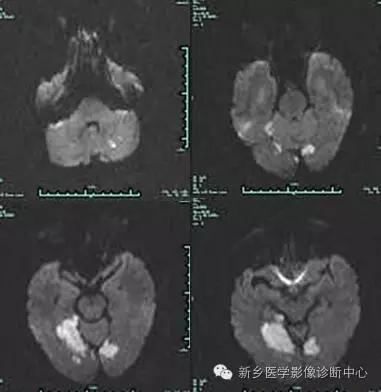

影像表现

影像表现:

脑部CT、MRI检查,显示累及基底动脉尖部5条血管供血区的2个以上梗死灶。常见部位依次为:丘脑、中脑、小脑、枕叶、颞叶等。

最大特征为双侧丘脑梗死,病灶位于丘脑中心部位,成蝶形、对称性分布。